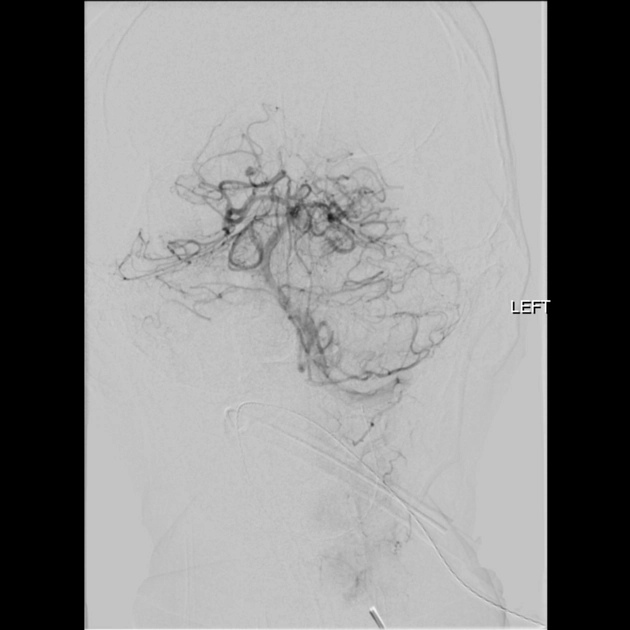

• Phình mạch não do nhiễm trùng (Intracranial Mycotic Aneurysm / Intracranial Infectious Aneurysm)